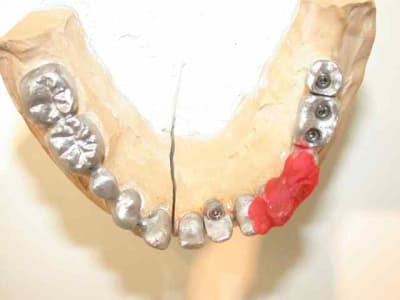

moulage panoramique...

on évoluera par étapes :

1)mise en pace de 3 implants 35 36 37

2) on garde 34 pour stabiliser l'appareil

3)on attend l'ostéointégration des implants.

pano après